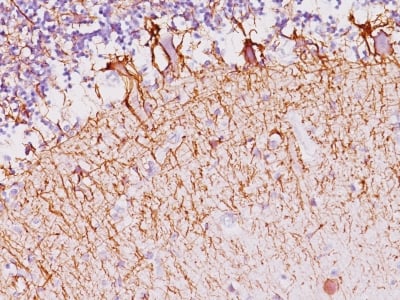

This MAb reacts with a 200kDa protein, identified as heavy sub-unit of neurofilaments (NF-H). Neurofilaments make up the main structural elements of axons and dendrites and are found in neurons, peripheral nerves, and sympathetic ganglion cells. Neurofilaments consist of three major subunits with molecular weights of 68kDa (NF-L), 160kDa (NF-M) and 200kDa (NF-H). Anti-neurofilament stains a number of neural, neuroendocrine, and endocrine tumors. Neuromas, ganglioneuromas, gangliogliomas, ganglioneuroblastomas, and neuroblastomas stain positively for anti-neurofilament. Neurofilaments are also present in paragangliomas as well as adrenal and extra-adrenal pheochromocytomas. Carcinoids, neuroendocrine carcinomas of the skin, and oat cell carcinomas of the lung also express neurofilament.

Brain, Neuroblastoma